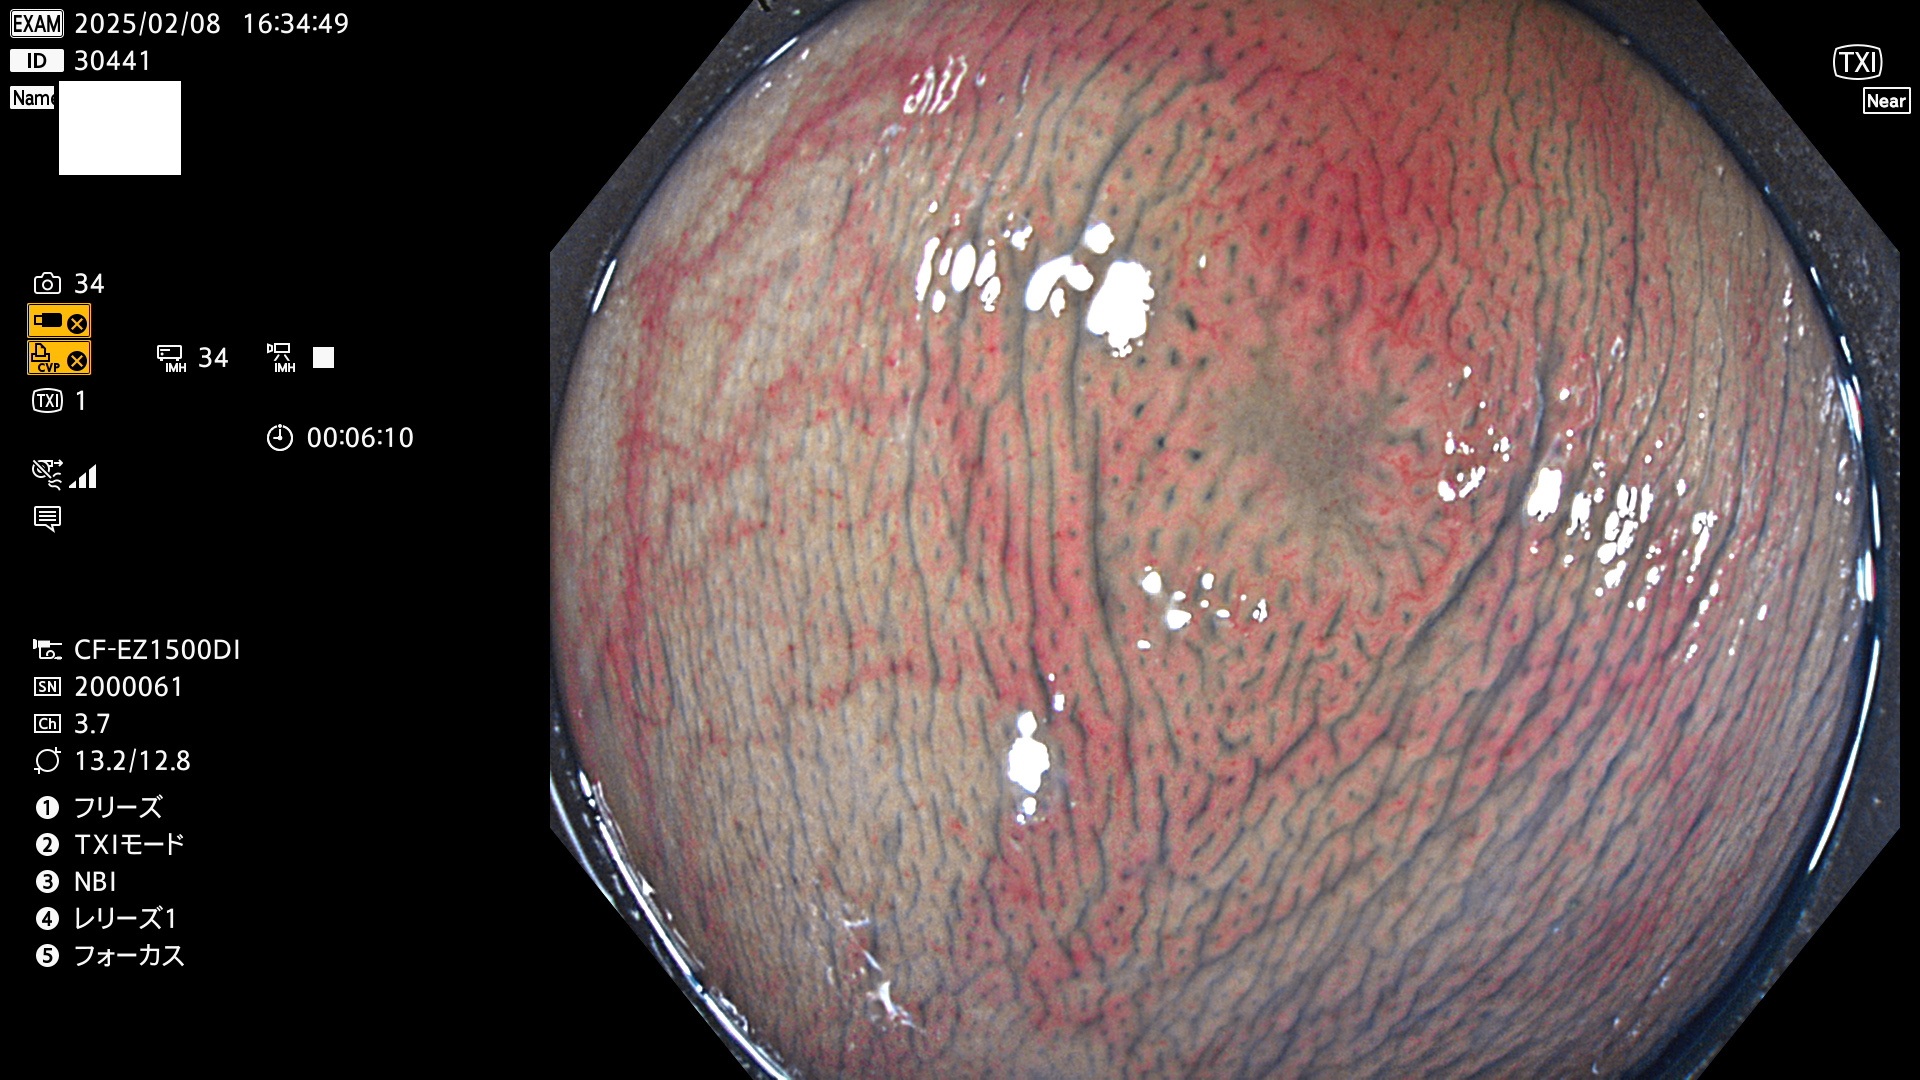

完全に平坦な物をUb、陥凹している物をUcと呼びます。最も発見が難しく危険な病変です。

毎週の検査(木・金・土・日)に発見されたUb、Uc型・腺腫を、その週の日曜の夜にUPし1週間、提示します。

抽出の対象期間 2025年2月6日〜2月9日の4日間(48件の検査)7個 (7/48=14%)